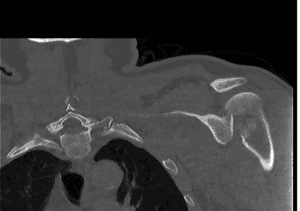

- Imaging:

- X-rays: Standard views to assess the fracture and dislocation.

- CT Scans: For detailed images.

- CT Angiography: Useful for identifying vascular structures in certain fracturepatterns.